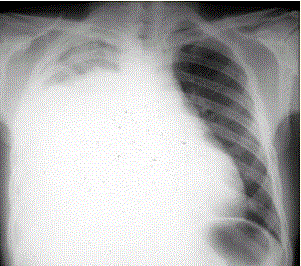

问题 患者男,34岁。进行性胸闷、气促1个月余,伴有干咳、右胸隐痛以及消瘦,无咯血、发热、盗汗、潮热等。 (提示 胸部X线检查如图所示) 该患者的初步诊断是

选项 A.右侧大量胸腔积液 B.右侧气胸 C.右侧肺不张 D.右侧液气胸 E.右侧大叶性肺炎 F.肺血栓栓塞症 G.右侧气胸

答案 A